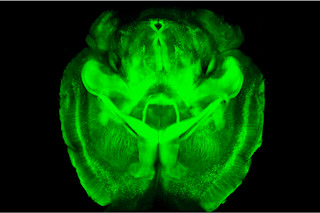

Into this murky mess, Stanford University neurobiologist Karl Deisseroth has brought CLARITY, a technique that turns brain tissue transparent while maintaining its structure. The method, described in Nature in April, makes it possible to inspect the 3-D architecture of an intact mouse brain in microscopic detail.

The result: a brain like glass, visible in fine detail without slicing and dicing. Deisseroth says the technique will help reveal faulty connectivity in neurological and psychiatric diseases like autism by making it easier to study brain wiring. In studying these diseases, he says, “A limitation has been: How are circuits wired up?”